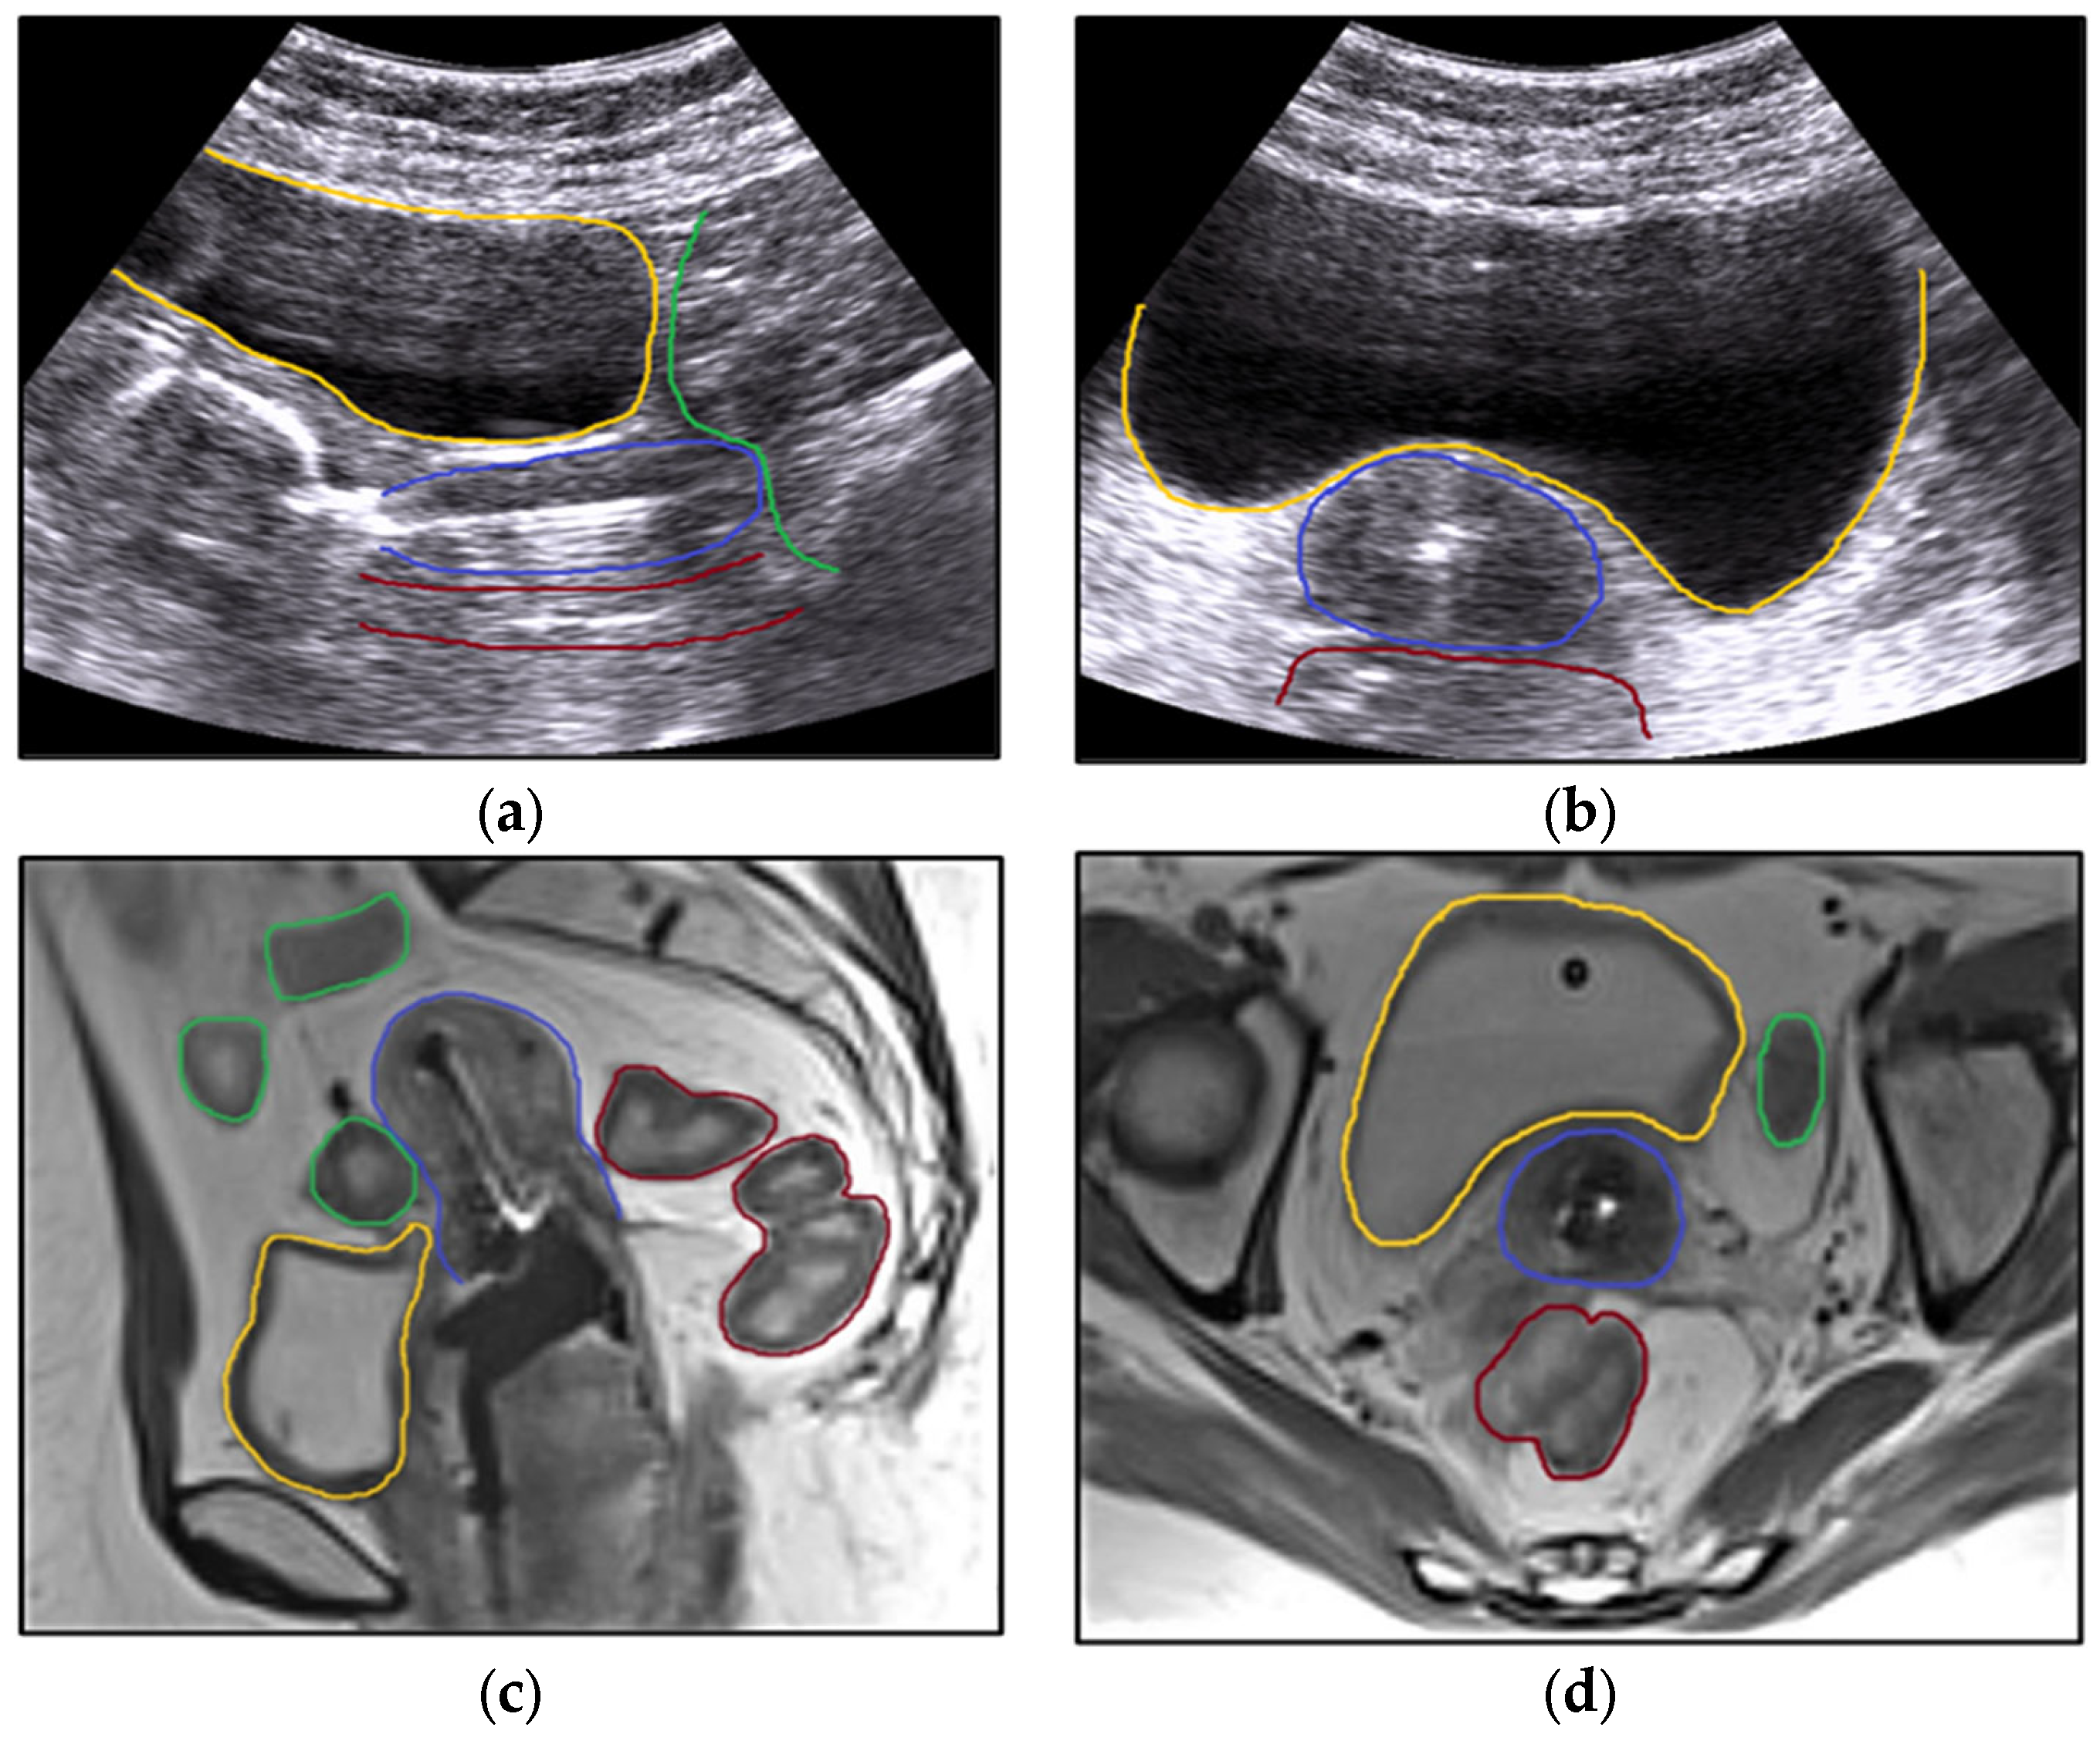

Figure 6.

A clinical situation when the Fletcher applicator was used. Sagittal (a) and axial (b) view with the applicator in the uterine canal on transabdominal ultrasound and sagittal (c) and axial (d) pelvic MRI. The fundamental principles pertaining to the implantation of intracavitary brachytherapy are shown. Measuring the uterine canal and taking precautions to prevent perforation is advantageous, particularly when considering the organs that are vulnerable (a,b). MRI pictures provide a clearer identification of the relationship between the organs at risk (c,d). Organs at risk are the bladder (yellow), rectum (brown), and bowel (green). During brachytherapy insertion, the bladder is filled with 400 mL of saline to bring the uterus (blue) into a vertical position (a,b), while with MRI, the bladder is filled with 50 mL of saline (c,d). The applicator is fixed using vaginal gauze packing.